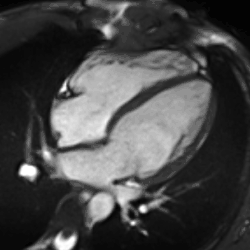

Heart function using cine imaging

Functional and structural information is acquired using bSSFP cine sequences. These are usually retrospectively-gated and have intrinsically high contrast in cardiac imaging due to the relatively high T2:T1 ratio of blood compared to myocardium. Images are typically planned sequentially to achieve the standard cardiac planes used for assessment. Turbulent flow causes dephasing and signal loss allowing valvular disease to be qualitatively appreciated. The left ventricular short axis cines are acquired from base to apex and are used for quantifying end-diastolic and end-systolic volumes, as well as myocardial mass. Tagging sequences excite a grid pattern that deforms with cardiac contraction allowing strain to be assessed.

Enlarged right ventricle with poor function in a patient with repaired tetralogy of Fallot by CMR